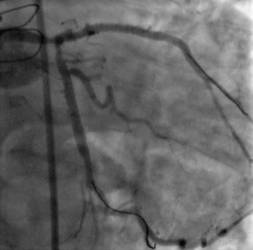

Para poder entender su utilidad debemos tener en cuenta que una de las mayores dificultades a las que se enfrentan los especialistas a la hora de colocar un stent reparador de una lesión coronaria son las zonas calcificadas, que dificultan la entrada del propio stent en la arteria. Partimos del hecho de que el 95% de los pacientes con obstrucciones arteriales son tratados mediante angioplastia coronaria e implante de stent. Sin embargo, entre ellos, se dan casos con un grado de calcificación de las obstrucciones tan alto que el acceso se hace realmente complicado. Y es precisamente en estas ocasiones cuando la aterectomía rotacional se hace más útil, e incluso necesaria, ya que el Rotablator pulveriza las placas calcificadas, dejando intactas el resto de zonas de la pared artificial, y dejando el camino libre para el paso del stent.

Aunque, como es natural, se puede aplicar siempre que sea necesario una desobstrucción, "este tipo de técnicas permite que cada vez podamos tratar pacientes más complejos, incluyendo individuos de mayor edad, con más factores de riesgo cardiovascular e, incluso, los que ya han sido sometidos a otras cirugías cardiacas, cuyas obstrucciones coronarias tienen años de evolución y, por tanto, el riesgo de una segunda intervención es muy alto", tal y como nos comenta la especialista.